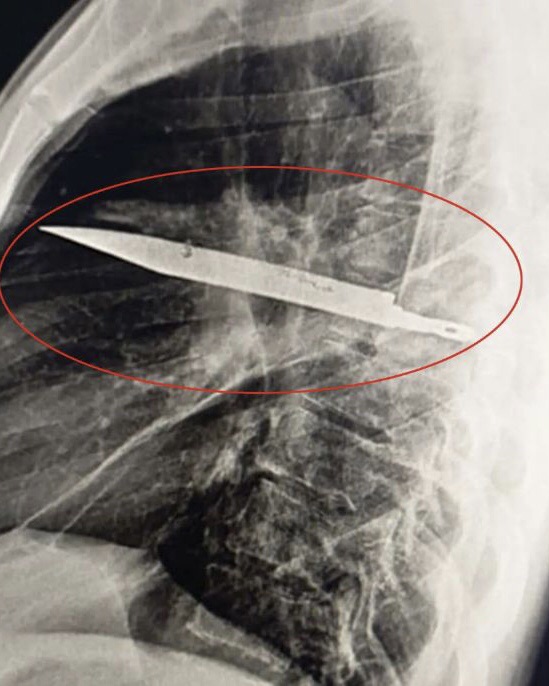

Fue la reciente aparición de pus maloliente lo que finalmente lo llevó a buscar ayuda médica avanzada. Una radiografía de tórax reveló la impactante verdad: un objeto metálico, descrito como una «especie de bisturí» o la hoja de un cuchillo, estaba incrustado en su cavidad torácica. La hoja había ingresado por la escápula y se encontraba rodeada de pus y tejido necrótico. Los cirujanos intervinieron de inmediato para extraer el arma y drenar la infección. Tras una exitosa operación y diez días de hospitalización, el paciente fue dado de alta sin complicaciones.